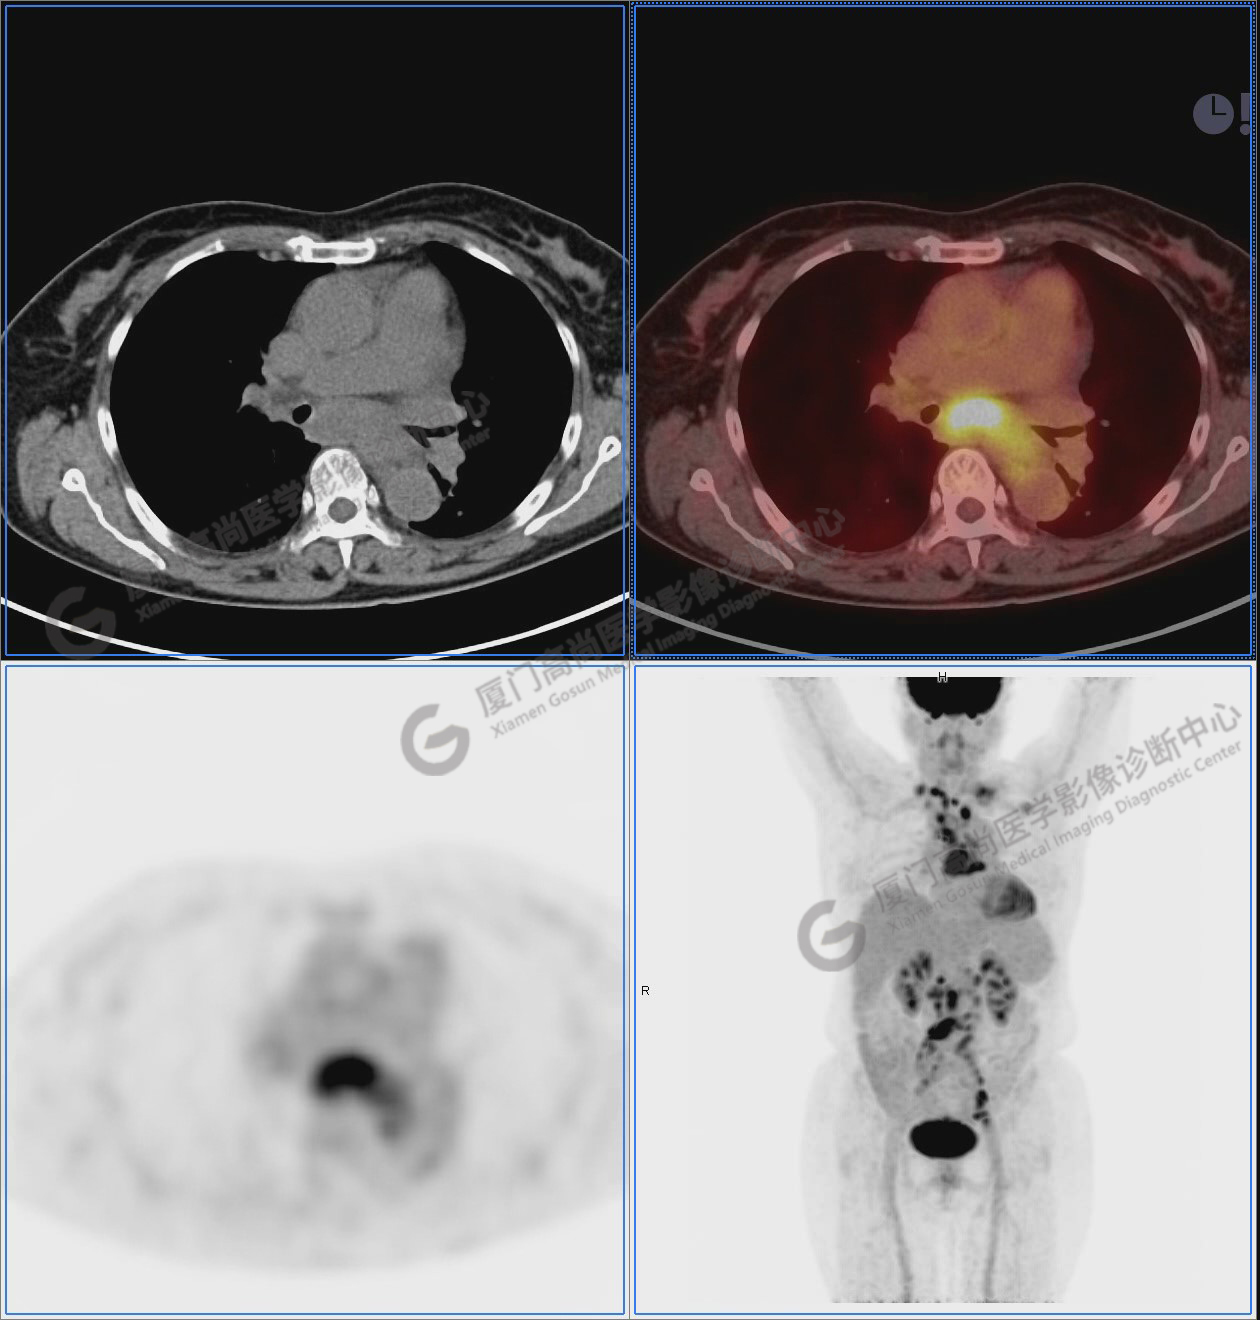

圖1:PET/CT全身圖像

圖2:雙側(cè)頸部多發(fā)增大淋巴結(jié),代謝不同程度增高,考慮為轉(zhuǎn)移。